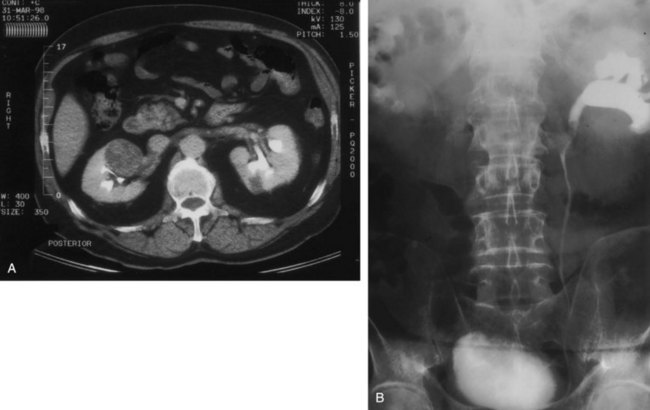

Although intravenous pyelography has been the traditional means for diagnosis of upper tract lesions, computed tomographic (CT) urography is increasingly performed today. CT is easier to perform and less labor intensive than intravenous pyelography. It also has a higher degree of accuracy in determining the presence of renal parenchymal lesions. On the other hand, small urinary filling defects (<5 mm) may be missed between the “cuts” of the traditional CT scan. More recently, CT urography has been performed to obtain a three-dimensional image of the upper tracts. This technique appears to be equal to intravenous pyelography in imaging the ureters and renal pelvis (McTavish et al, 2002). With CT urography, the sensitivity for detecting upper tract malignant disease has been reported to approach 100%, with a specificity of 60% and a negative predictive value of 100% (Caoili et al, 2002). CT urography does, however, expose the patient to higher doses of radiation.

Radiolucent filling defects, obstruction or incomplete filling of a part of the upper tract, and nonvisualization of the collecting system are the typical findings suggestive of an upper urinary tract tumor. Filling defects, which account for 50% to 75% of cases, typically require the intravenous administration of contrast material to be identified (Murphy et al, 1981; Fein and McClennan, 1986). The differential diagnosis of these defects includes blood clot, stones, overlying bowel gas, external compression, sloughed papilla, and fungus ball. Stones can be ruled out most easily by confirmation of calcification by renal ultrasonography or CT. TCCs have an average density of 46 Hounsfield units (HU) and a range of 10 to 70 HU (Lantz and Hattery, 1984). This is in contrast to an average of 100 HU seen in radiolucent uric acid stones (range, 80 to 250 HU). Thus CT can be useful in distinguishing between these two common causes of radiolucent filling defect on excretory urography or retrograde ureterography. The impact of hydronephrosis and nonvisualization for renal pelvis tumors versus ureteral tumors as indicators of a higher stage is uncertain. Nonvisualization is reported in 20% of renal pelvis tumors, only 33% of which are invasive (McCarron et al, 1983). Nonvisualization is reported in 37% to 45% of ureteral tumors and carried a 60% risk of invasion in one series (McCarron et al, 1983). In other reports there is no correlation of nonvisualization and stage (Batata and Grabstald, 1976; Anderstrom et al, 1989). Hydronephrosis with or without an associated filling defect is linked with invasion in 80% of ureteral tumors (McCarron et al, 1983; Cho et al, 2007).

Some have suggested that ultrasonography has sensitivity equal to that of urography in evaluating patients with painless gross hematuria for upper tract malignant disease (Yip et al, 1999; Data et al, 2002). For staging purposes, CT or magnetic resonance imaging (MRI) is most useful in determining the extent of invasion, an associated mass lesion outside the collecting system, and the presence of lymph node or distant metastases (Milestone et al, 1990). CT is also more sensitive than conventional radiography in determining minimally radiopaque substances, making it useful in identifying urine excreted by poorly functioning areas of kidney (as in obstructed areas) (Kenney and Stanley, 1987). The greatest downside of CT or MRI is in the detection of small lesions that may be lost in volume averaging. In one series, CT predicted TNM stage in 60% of patients; it understaged 16% and overstaged 24% (Scolieri et al, 2000).